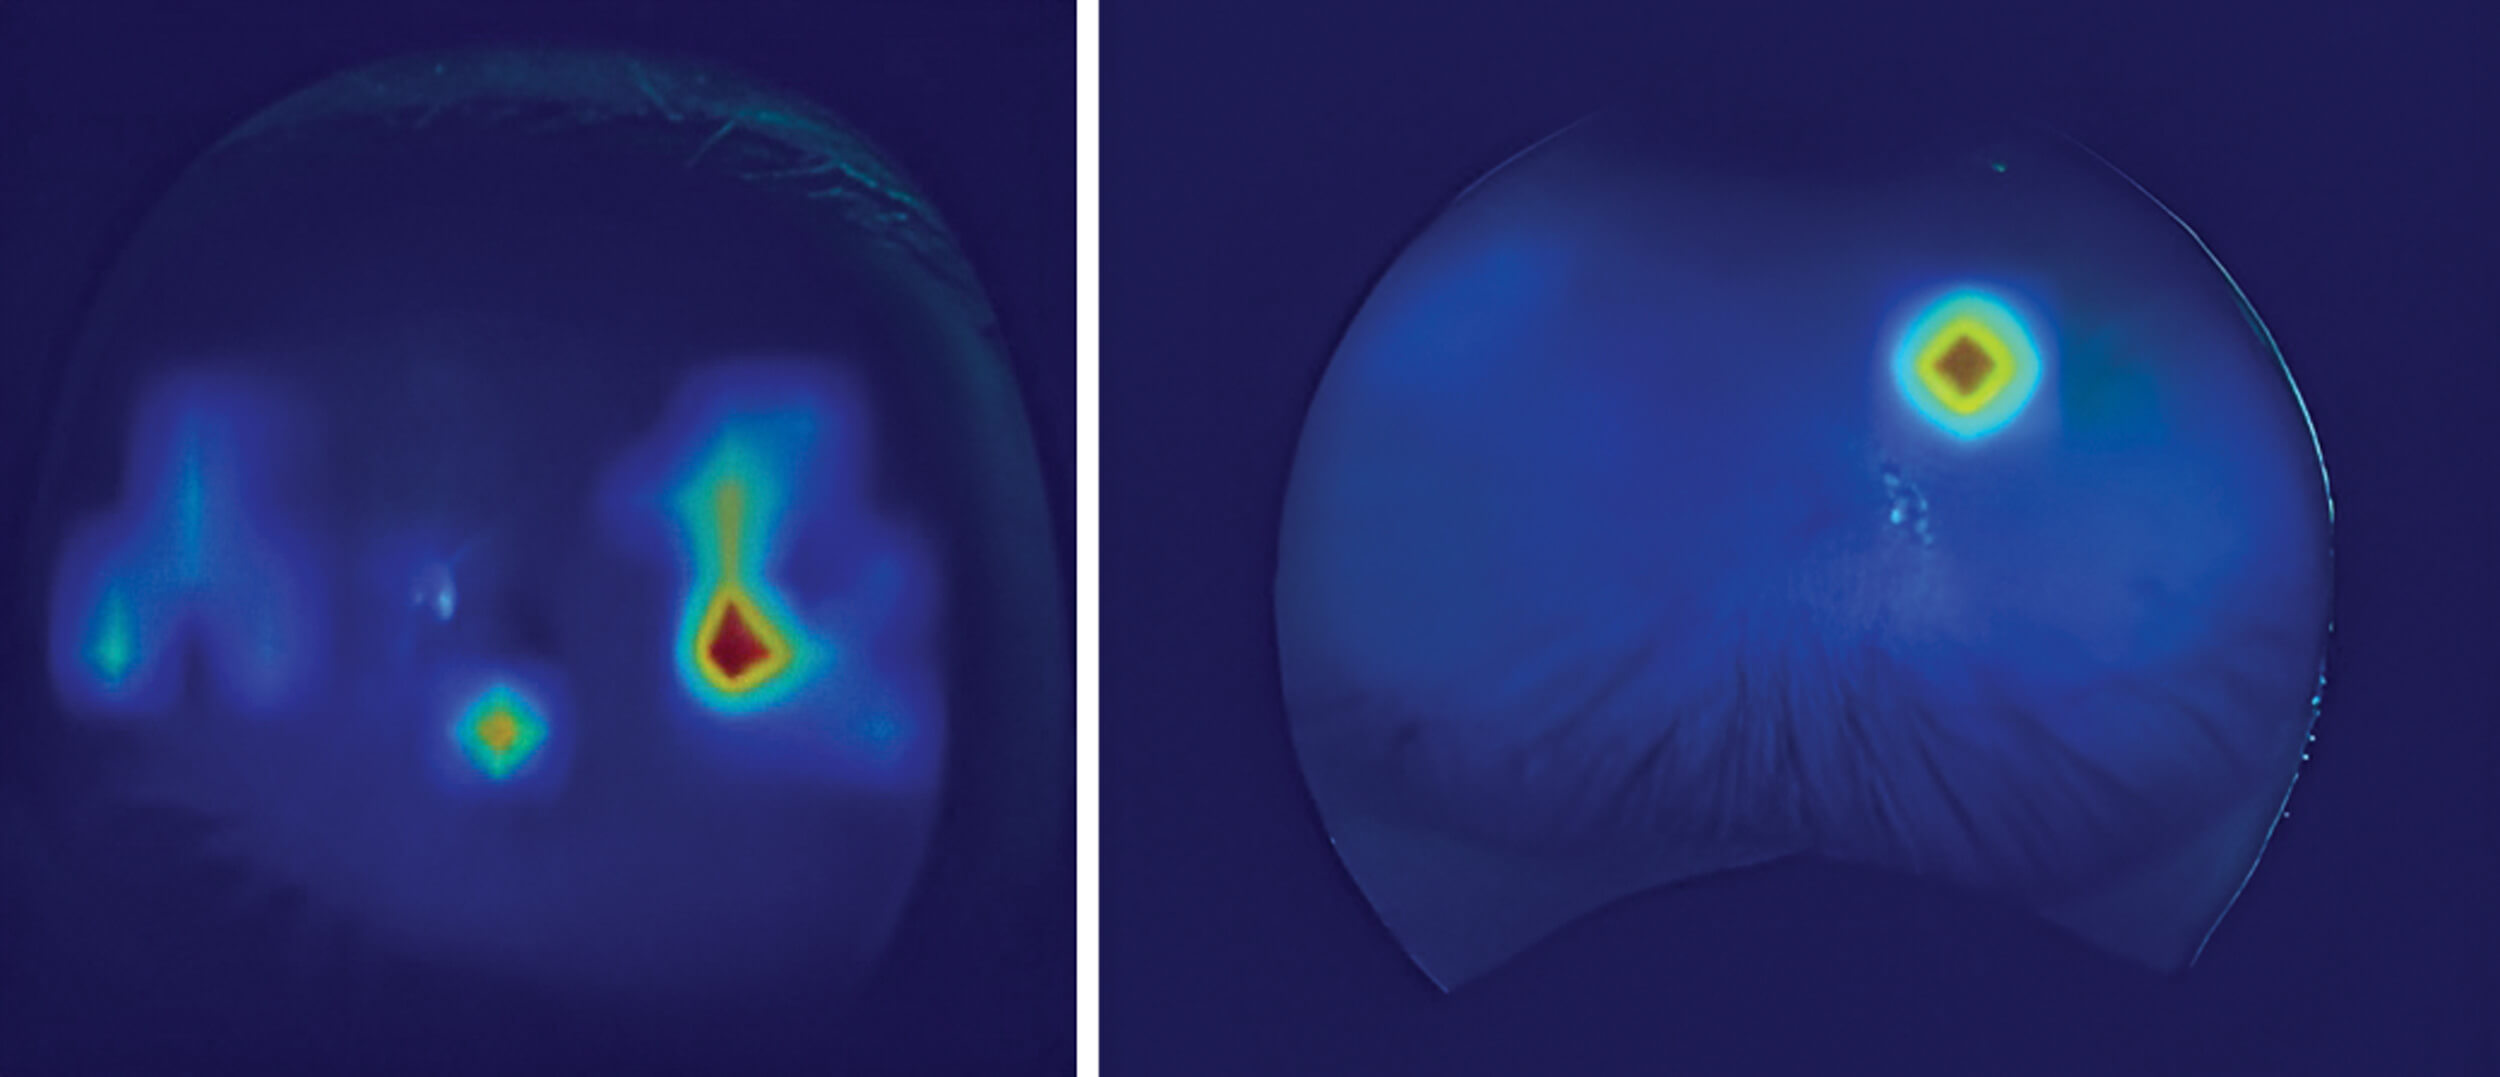

Figure 2: (a) Class activation map showing the models prediction of a tumour being present. (b) Class activation map showing the models prediction of a freckle being present.

Class activation maps, in this case Grad-CAM [7], allows us to visualise the decision-making process of the model. In Figure 2, for instance, the model focuses on specific regions of the lesion that might be overlooked by the human eye. In Figure 2a, the model identifies a small area within the freckle, leading to an 81% certainty that it is benign. Conversely, Figure 2b shows an 82% certainty of UM, with the model also factoring in darker regions surrounding the fovea - an area that could hold key differentiating features. These maps are one of the many ways of regulating a real-world model with these being output at the time of diagnosis. A manual check by a clinician on these images would also help the model to make correct decisions.